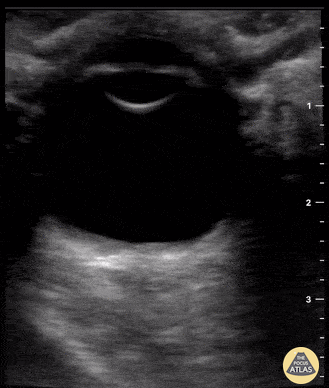

Orbital - ONSD normal ICP

Patient presented with fall from standing height with resultant traumatic subarachnoid hemorrhage (SAH). POCUS of ONSD is reassuring in that ONSD is <5 mm, suggestive of no associated elevated intracranial pressure. Tessa W. Damm, DO. Intensivist. Milwaukee, WI @DrDamm